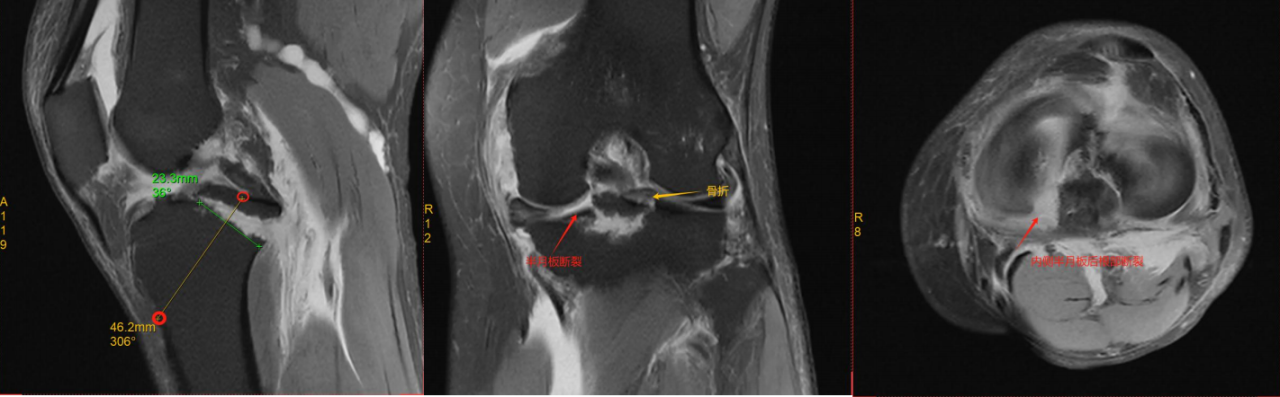

1.CT与MRI矢状位骨折块长度(BC);

2.矢状位撕脱骨折前后距与胫骨平台前后距比例(AE/AD);

ⅢB型:多块撕脱骨折;合并半月板撕裂;BC>15mm;AE/AD≥1/2。

术式: 双袢(后叉前建立骨道)+骨道固定

合并内侧半月板放射裂

撕脱骨折、内侧半月板放射裂

半月板骨道固定、双袢固定撕脱骨折